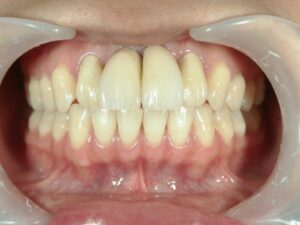

きれいな前歯が入りました。

患者さんは非常に満足されています。